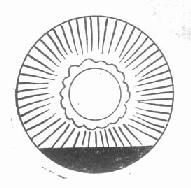

3.前房积血为虹膜睫状体血管破裂所致。微量出血仅可见房水中出现红细胞。出血较多时,血液积于前房的下部呈一水平面(图15-4)。根据积血占前房的容量可分为3级。少于前房容量的1/3为Ⅰ级;介子1/3~2/3级为Ⅱ级;多于2/3为Ⅲ级。或记录出血平面的实际高度(mm数)。严重时前房完全充满血液,呈黑色。临床上通常将外伤后立即发生的出血称为原发性前房出血;积血吸收后或在吸收过程中再次出血者,称继发性出血,多在伤后1周内发生。

图15-4 前房积血